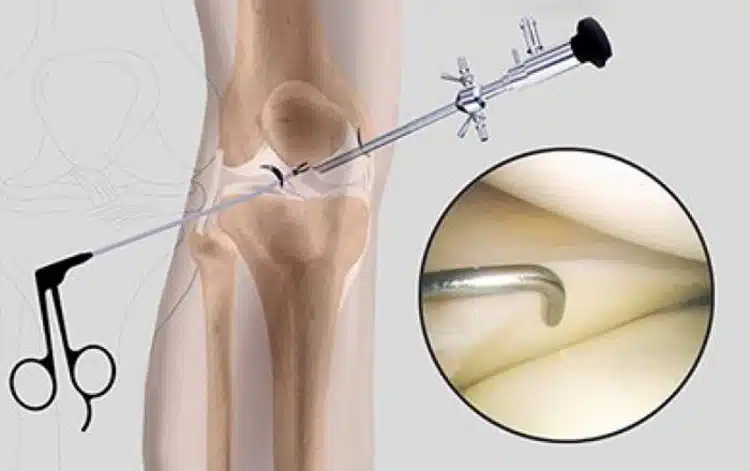

يعاني الكثير من الأشخاص من آلام الركبة الناتجة عن إصابات رياضية، أو خشونة مبكرة، أو تمزقات غضروفية، وغالبًا ما تكون الأعراض معقدة، ويصعب تحديد سبب الألم من خلال الفحص الظاهري وحده، من هنا، برز دور منظار الركبة كوسيلة دقيقة وفعالة في تشخيص وعلاج العديد من مشكلات المفصل دون الحاجة إلى جراحة تقليدية.

ما هو منظار الركبة؟

المنظار هو أداة طبية دقيقة تستخدم لفحص المفصل من الداخل عبر شق صغير لا يتجاوز سنتيمتر واحد، يحتوي على كاميرا دقيقة وضوء، وينقل من خلاله صورة حية لشاشة خارجية، مما يتيح للطبيب رؤية الأنسجة الداخلية للمفصل مباشرة دون الحاجة لفتح الركبة بشكل واسع، وقد تطور هذا الإجراء ليصبح أداة مزدوجة تستخدم للتشخيص والعلاج، ما يجعله من أهم التقنيات الحديثة في جراحة العظام.

يتيح المنظار للطبيب رؤية غضاريف الركبة، الأربطة، الغشاء الزليلي، والأسطح المفصلية بدقة، ما يساعد في تحديد أسباب الألم أو التيبس التي قد لا تظهر بوضوح في الأشعة أو الرنين المغناطيسي.

- التعقيم والشق الجراحي: يجرى شق صغير لإدخال المنظار، وشق آخر لإدخال أدوات دقيقة.

- فحص المفصل: يتم تحريك الكاميرا داخل المفصل لمعاينة الغضاريف، الأربطة، وتجويف المفصل.

- العلاج الفوري: عند الحاجة، تستخدم أدوات دقيقة لإزالة أو تعديل الأنسجة التالفة.